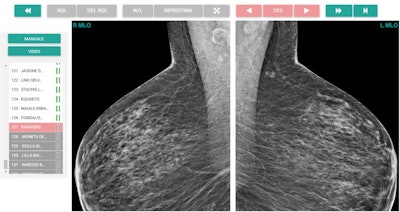

![Region-of-interest delineation in a magnified craniocaudal projection. No more than one region of interest can be placed on each projection. If a case is left with a region of interest placed on a mammographic projection, it will be classified as true positive if the region of interest matches the one previously delineated during dataset building for the actual presence of carcinoma; otherwise, the case will be classified as a false positive. To store the case as a negative one and move on to the next one, the reader can click on the button with white arrowheads on green background (shown at the right end in top figure [Example of mediolateral oblique projection magnification]). The case will be classified as true negative if carcinoma is not actually present, otherwise as a false negative.](https://img.auntminnieeurope.com/files/base/smg/all/image/2021/09/ame.2021_09_10_19_02_6235_2021_09_13_womens_insider_Figure3.png?auto=format%2Ccompress&fit=max&q=70&w=400)